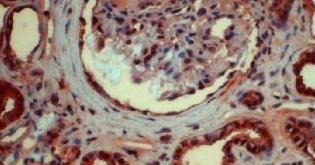

下圖為腎樣本中咪唑啉酮著色的AGE

AGE是糖尿病早期風(fēng)險(xiǎn)測(cè)評(píng)的重要生物標(biāo)志。

在胰島素抵抗(IR)、糖調(diào)節(jié)受損IGR(和糖尿病者體內(nèi)),AGE加速形成。產(chǎn)生的過(guò)量AGE通過(guò)直接或間接作用,導(dǎo)致多種病理反應(yīng),成為糖尿病并發(fā)癥的重要致病因素。